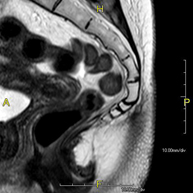

Prueba diagnóstica no invasiva que consiste en la obtención de imágenes de alta definición anatómica del sistema urinario mediante el empleo de un campo electromagnético y ondas de radio (con un emisor y un receptor). No utiliza radiación ionizante. Requiere el uso de contraste paramagnético (Gadolinio) que se excretará por el sistema urinario y nos permitirá obtener imágenes en 2D y 3D. - RM Próstata

Prueba diagnóstica no invasiva que consiste en la obtención de imágenes de alta definición anatómica de la glándula prostática mediante el empleo de un campo electromagnético y ondas de radio (con un emisor y un receptor). No utiliza radiación ionizante. Se utiliza una bobina endorrectal para obtener imágenes de máxima definición anatómica de la próstata, que permitirá realizar el estudio espectroscópico (estudio a nivel molecular que ayuda a diferenciar las células de origen maligno o tumoral). También se realiza el estudio con contraste paramagnético que aporta una mejor definición tisular. Esta prueba dura unos 40 minutos, durante los cuales el paciente deberá estar lo más quieto posible. Como preparación previa requiere limpieza del colon. Esta prueba está especialmente indicada en aquellos pacientes con sospecha de neoplasia de próstata, con neoplasia de próstata conocida para el estadiaje tumoral, estudio de localización del tumor prostático como guía o mapa para la biopsia, seguimiento de los pacientes con neoplasia de próstata tratados con tratamiento quirúrgico o radioterápico, sospecha de recidiva de la neoplasia de próstata, etc. - RM Cuerpo entero (Total body)